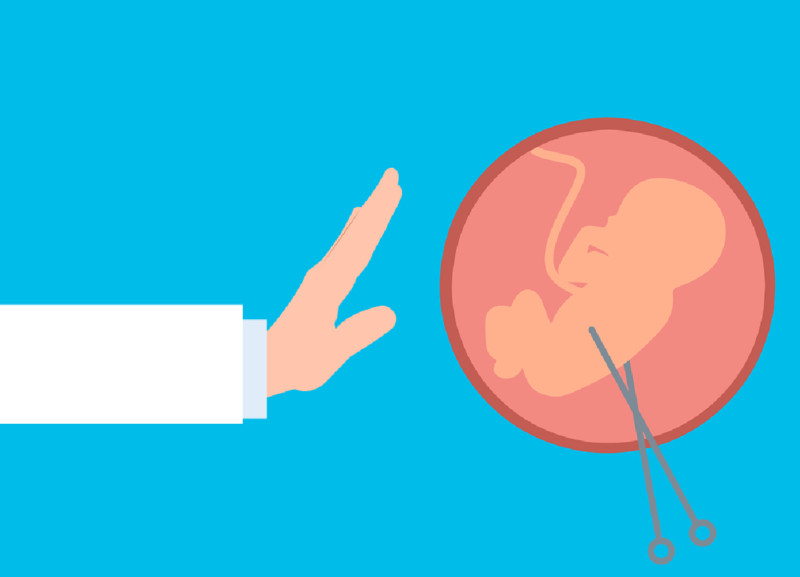

Safe Abortion Practices

Safe abortion practices refer to medical procedures and guidelines designed to terminate a pregnancy in a way that minimizes risks and ensures the health and well-being of the individual.

Safe abortion can be performed through medication or surgical methods, depending on the gestational age and the specific circumstances of the patient.

Accessing safe abortion services is crucial for preventing complications, such as infection or excessive bleeding, that can arise from unsafe practices.